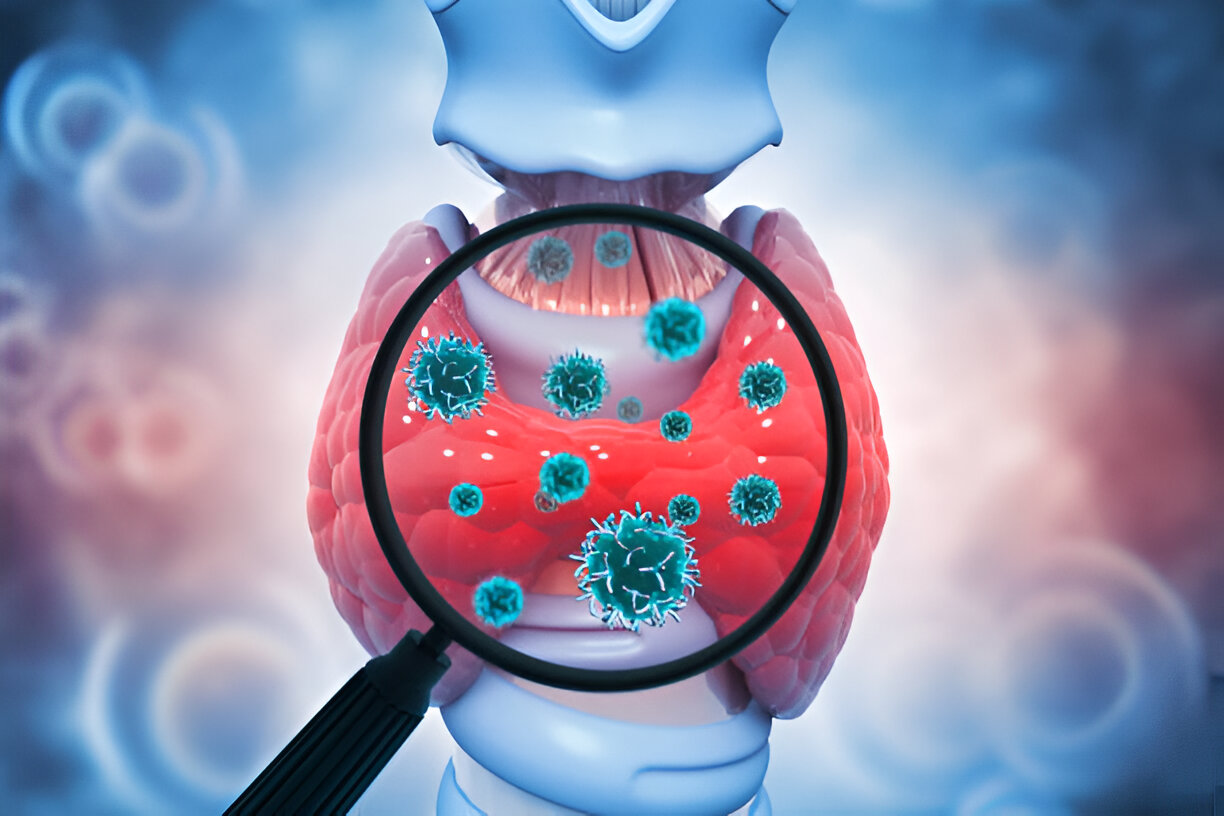

Thyroid gland is a small, butterfly shaped organ which is located at the base of the neck. The gland functions to produce hormones which regulates the important functions of the body. In this blog we will discuss the types, causes and symptoms of thyroid and thyroid disorders.

The thyroid gland is a butterfly-shaped gland which is located at the base of the neck and is responsible for producing hormones which regulate metabolism, energy levels and even mood. A thyroid nodule is a lump or growth which forms within the thyroid gland.

Thyroid disorders are among the most common endocrine issues worldwide, affecting millions of people, especially women. Whether it's hypothyroidism (underactive thyroid) or hyperthyroidism (overactive thyroid), these conditions can significantly impact your metabolism, energy levels, weight, and overall well-being.